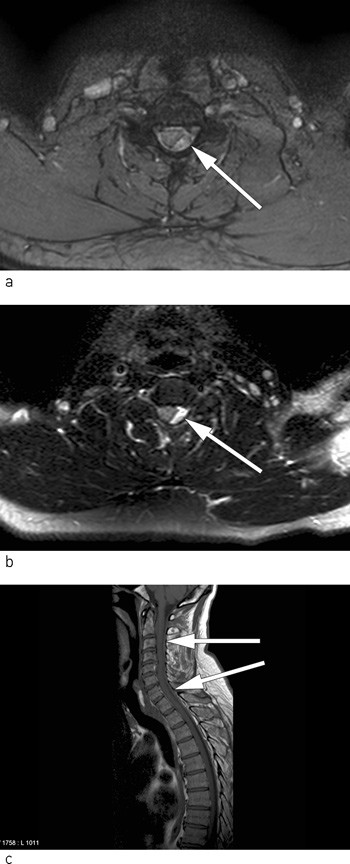

After thrombolysis the patient was placed in the Department of Neurology, and an MRI scan of the spinal cord was planned. Because of the time window for starting thrombolysis, an MRI of the spinal cord was not performed in advance. However, in the department the pareses in the right upper and lower limb increased, and it was decided to perform an acute MRI of the spinal cord and a further MRI of the brain. The MRI of the brain was still normal, but the MRI of the spinal cord showed congestion consistent with epidural haematoma located dorsally on the left side from the 3rd to the 7th cervical level. On images, the spinal cord is considerably compressed at the 4th and 5th cervical level (Fig. 2 a-c).

Figure 2  Epidural haematoma with mass effect on different MRI sequences a) and b) axial sections and c) sagittal section,…

Figure 2 Epidural haematoma with mass effect on different MRI sequences a) and b) axial sections and c) sagittal section, slightly parasagittaly to the left